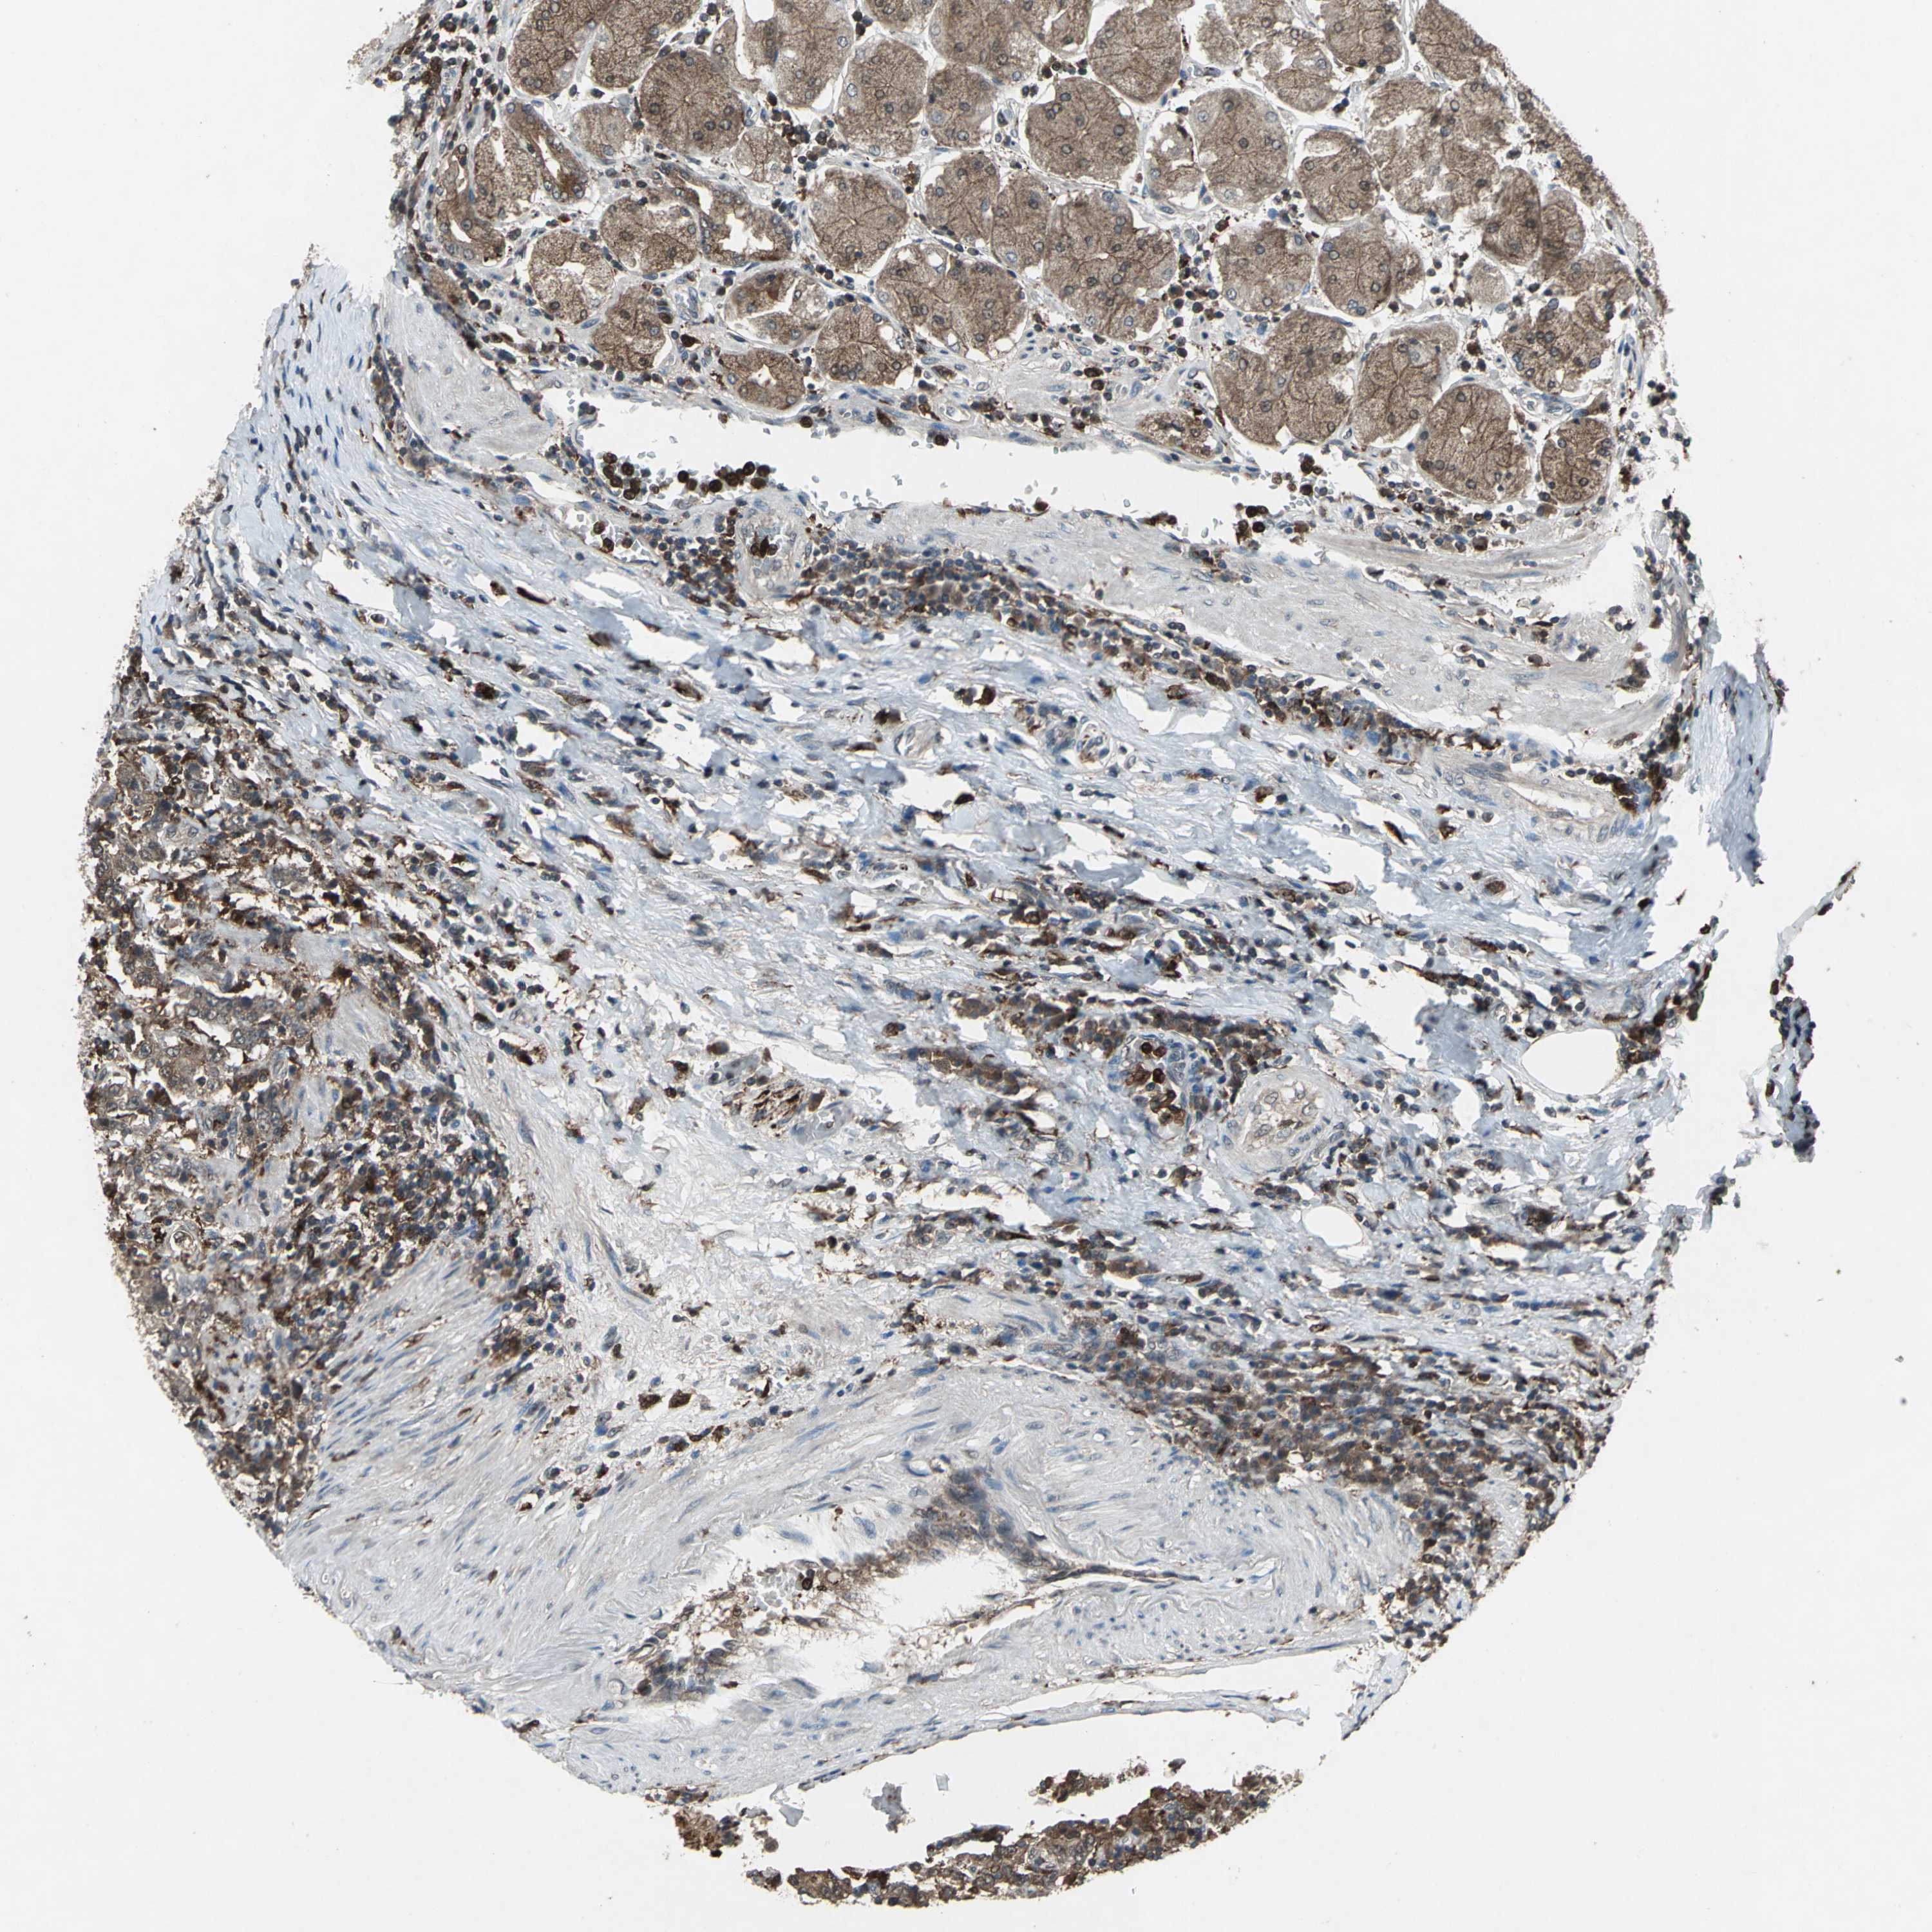

STOMACH CANCER - Protein expressioni

A mouse-over function shows sample information and annotation data. Click on an image to view it in a full screen mode. Samples can be filtered based on level of antibody staining by selecting one or several of the following categories: high, medium, low and not detected. The assay and annotation is described here.

Note that samples used for immunohistochemistry by the Human Protein Atlas do not correspond to samples in the TCGA dataset.

Antibody stainingi

Antibody staining in the annotated cell types in the current human tissue is reported as not detected, low, medium, or high, based on conventional immunohistochemistry profiling in selected tissues. This score is based on the combination of the staining intensity and fraction of stained cells.

Each image is clickable and will lead to virtual microscopy that enables deeper exploration of all samples and also displays staining intensity scores, fraction scores and subcellular localization as well as patient and tissue information for each sample.

Antibody HPA049074

Antibody HPA054496

Antibody CAB006853

Antibody CAB015948

Staining

High

Medium

Low

Not detected

Intensity

Strong

Moderate

Weak

Negative

Quantity

>75%

75%-25%

<25%

None

Location

Nuclear

Cytoplasmic/membranous

Cytoplasmic/membranous,nuclear

Adenocarcinoma, NOS

Adenocarcinoma, High grade